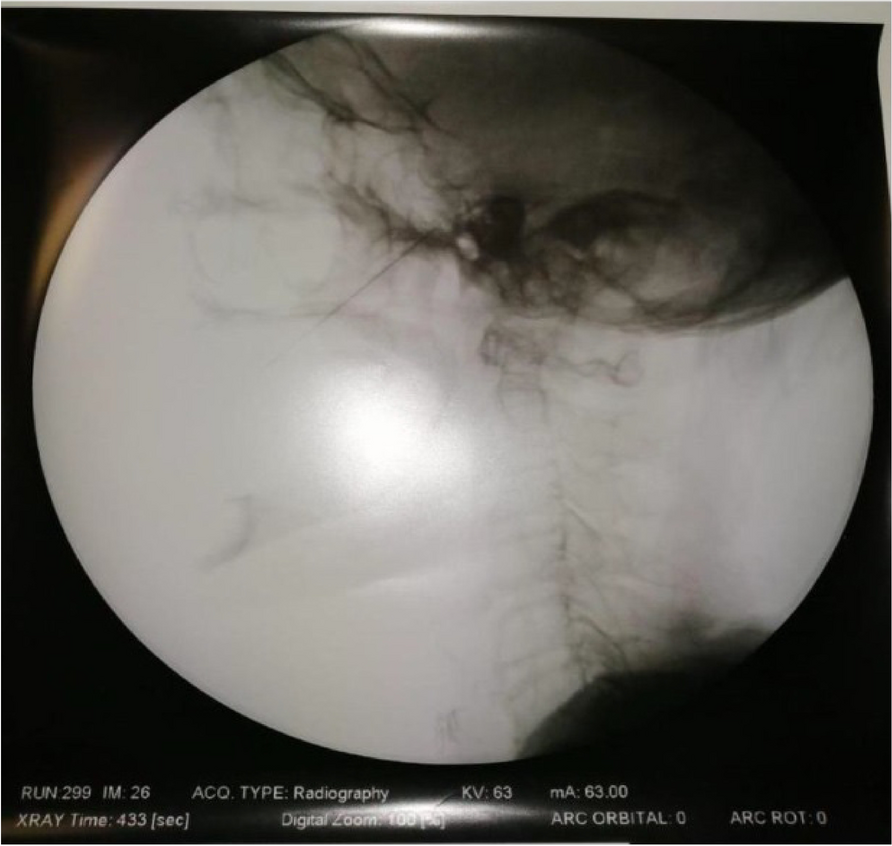

A few hours after the admission in ICU he reported a blunt abdominal pain, mainly on the right side, nausea and the exams showed increased amylase levels, urologists excluded any surgical involvement of pancreatic tissue and suspected a transient sphincter of Oddi dysfunction [3]. After one night in ICU he was transferred to the urology ward due to his clinical stability, even though Amylase peaked at 2340 U/l. Two days later abdominal pain increased to severe, with characteristics of peritonism and increased inflammatory markers. An abdomen-thorax CT scan revealed acute pancreatitis (AP) (Figure 1) and he was transferred to ICU. He started a standard treatment for acute pancreatitis and antibiotic therapy [4].

On postoperative day nine, due to general deterioration of clinical conditions and further anemization that required blood transfusion, he underwent an emergency laparotomy, in which propofol was not used as an anesthetic drug, that found a completely necrotic pancreas. The following day he faced a multi organ failure (MOF) which rapidly led to death. Consent to publish the case report was accorded by the family.

Acute pancreatitis (AP) Is a complex and severe disease with a high mortality rate [4]. Propofol, is a common anesthetic drug which is widely used in daily practice for sedations and general anesthesia [5], few cases of Propofol Induced AP have been published, in which the diagnosis has been made excluding more common causes [6].

In fact, Propofol is listed as a possible cause of AP, class Ib, based on the classification of Badalov et al. [7]. Following the scheme proposed by the systematic review by Haffar et al for Propofol induced AP [6] we could confirm that our hypothesis is plausible. He satisfied the American College of Gastroenterology criteria for AP [8,9] and it is classified as severe acute pancreatitis according to the Revised Atlanta Classification with peripancreatic necrotic fluid collection [10]. Marshall score [11] after admission was two and Naranjo et al [12] probability scale for drug adverse reaction was three, meaning that the adverse reaction is possible. Latence according to Badalov et al [7] has been short or intermediate. Exclusion of other plausible causes, timing of pancreatitis symptoms and previous cases in literature support our hypothesis of propofol induced pancreatitis.